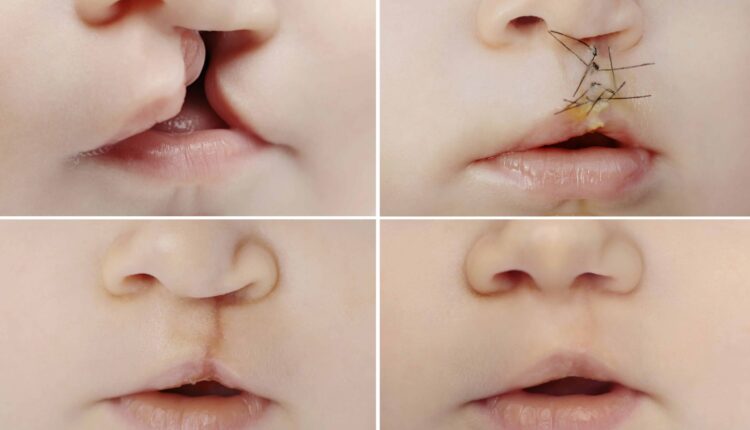

این دسته از دفورمیتی مادرزادی اعضای بدن را تحت تاثیر قرار میدهند. نقص عضو، نقص قلب، نقص لوله عصبی، مشکلات معده و روده و شکاف لب یا کام از مهمترین بیماریهای مادرزادی ساختاری هستند.

از قدرت جراحی در درمان ناهنجاریهای مادرزادی یا کاهش علائم آن نباید غافل بود. نقایص قلبی و ناهنجاریهای فیزیکی نظیر شکاف لب از جمله بیماریهای مادرزادی هستند که با کمک جراحی قابل درمان هستند. به واسطه پیشرفت تکنولوژی میتوان با انجام جراحیهای درونرحمی (نوزادی که هنوز در رحم مادر است) نظیر اسپینا بیفیدا اسباب درمام اثربخش برخی ناهنجاریها را فراهم کرد.